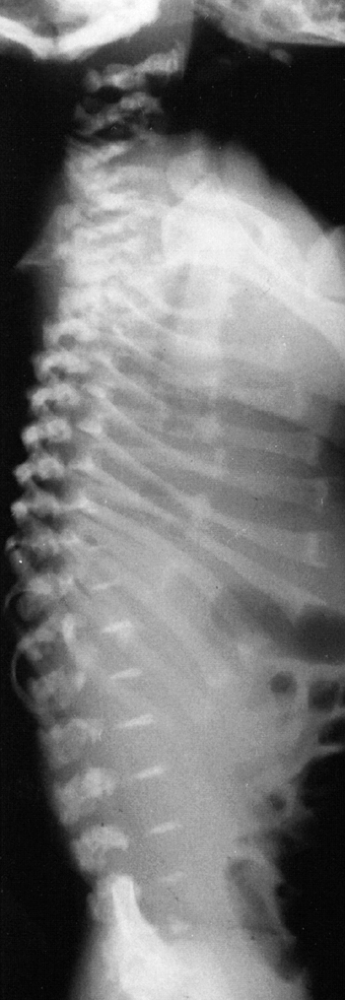

The posterior arches of the lower cervical spine are often bifid. There

are no external clues to this underlying abnormality, which is occult.

Cervical kyphosis is seen in one third to one half of patients (8,91);

this disorder may be present in infancy, and its course is variable.

Spontaneous resolution has been reported in a number of patients, even

in those with curves of up to 80 degrees (92,93) (Fig. 8.16 A, B). However, other cases progress, and there are several reports of quadriparesis resulting from this deformity (8,94). Scoliosis develops in at least one third of patients (91),

![]() |

|

Figure 8.16 Cervical kyphosis in a 1-year-old child (A)

with diastrophic dysplasia is pronounced, with marked deformity of C4. The findings of neurologic examination are normal. Four years later, the condition is markedly improved without any intervention (B), and 7 years later the vertebral bodies have been restored to nearly normal shape, although the canal remains narrow (C). |